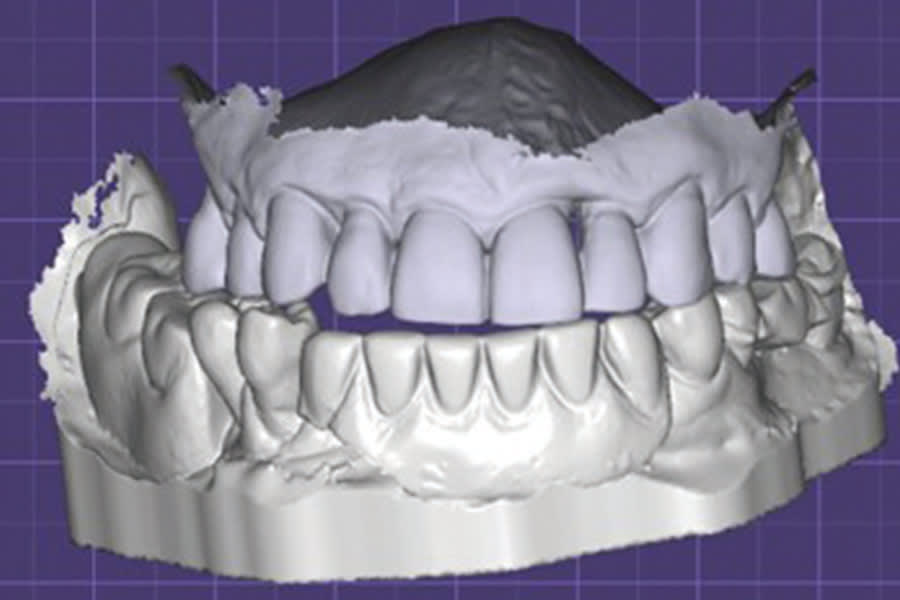

The intraoral scans were imported into DTX Studio software (DEXIS) to begin the implant and prosthesis planning (Figures 2 and 3). A virtual prosthesis was designed to articulate with the maxillary dentition (Figure 3). Implants were planned at four sites in the mandibular arch (Figure 1).

The previous virtual-designed prosthesis was merged with the scan of the implants. Modification of the hybrid design was accomplished creating the intaglio surface related to the implant connections and soft tissue (Figures 6 and 7). Emergence of the screw-access holes on the occlusal surface allowed sufficient prosthetic material around them to prevent fracture of the prosthesis during function (Figure 7). The virtual implant analogs were removed virtually, and the prosthesis design was completed in preparation for printing (Figure 8 through Figure 10). The hybrid prosthesis was printed on the Pro 55 S printer, utilizing OnX Tough 2.0 resin. Following 3D printing, the prosthesis was removed from the build plate with its supports present (Figure 11). The supports were removed with an acrylic bur and the surfaces were finished (Figures 12 and 13). Akzent LC gingival tone resin (VITA North America) was applied to the gingival aspects of the hybrid prosthesis and cured to provide a natural esthetic appearance.